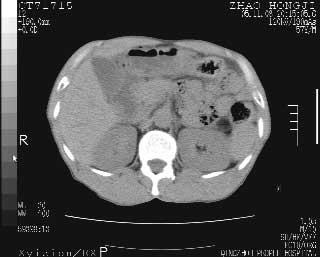

临床资料:男性,57岁,上腹部疼痛并5天,突然加重并延及全腹伴恶心5小时入院。胰淀粉酶化验在正常范围。检查:腹肌紧张,全腹压痛、反跳痛,尤以右上腹部为著。肠鸣音减低。血常规:wbc14.6x10/9, n:11.3x10/9 ,血压:135/90mmhg. 胸部透视:腹部肠腔轻度张气,未见其它异常改变。

肝右前缘少量积气,其他未见明显异常.考虑上消化道穿孔.

小网膜囊积气液,胃壁僵硬。考虑胃穿孔。

小膜网膜积液,肝缘气腹征,上消化道穿孔。

胰腺形态规则,胰周脂肪间隙清晰,结合临床可排除急性胰腺炎

从图提示我同意空腔脏器穿孔的诊断,来源肠道{由于病程较短,故没能见到肠系膜聚局的征象}。

肝缘见少许气体,胰尾部见少许气体包饶(蓝色圈),12指肠上部或球部邻近胆囊周边也可见少许气体影(黄色圈),并忖托出胆囊壁,12指肠远段肠道内未见明显气体(白色箭)。

肝脏前缘见少量积气、胰尾部见少许气体包饶,肾前筋膜未见增厚,临床淀粉酶不高,意见:上消化道穿孔。

消化道穿孔。12指肠球部周和胰周积气考虑12指肠穿孔可能性大。

入院3小时后行剖腹探查术,见腹腔内大量脓性混浊液约1000ml,十二指肠球部溃疡穿孔,溃疡面约2.5x2cm,穿孔直径约0.6cm。胃内容物外益,周围组织炎性水肿明显。行十二指肠穿孔修补术。术后诊断:

1、十二指肠溃疡穿孔

2、弥漫性腹膜炎

对于少量的腹腔游离气体,ct检查较普通透视有绝对的优势,它不仅可以看到肝脏前上缘的气体,而且还能够看到小网膜区的游离气体。从而可以肯定诊断。各位分析战友的很好,感谢大家的参入!